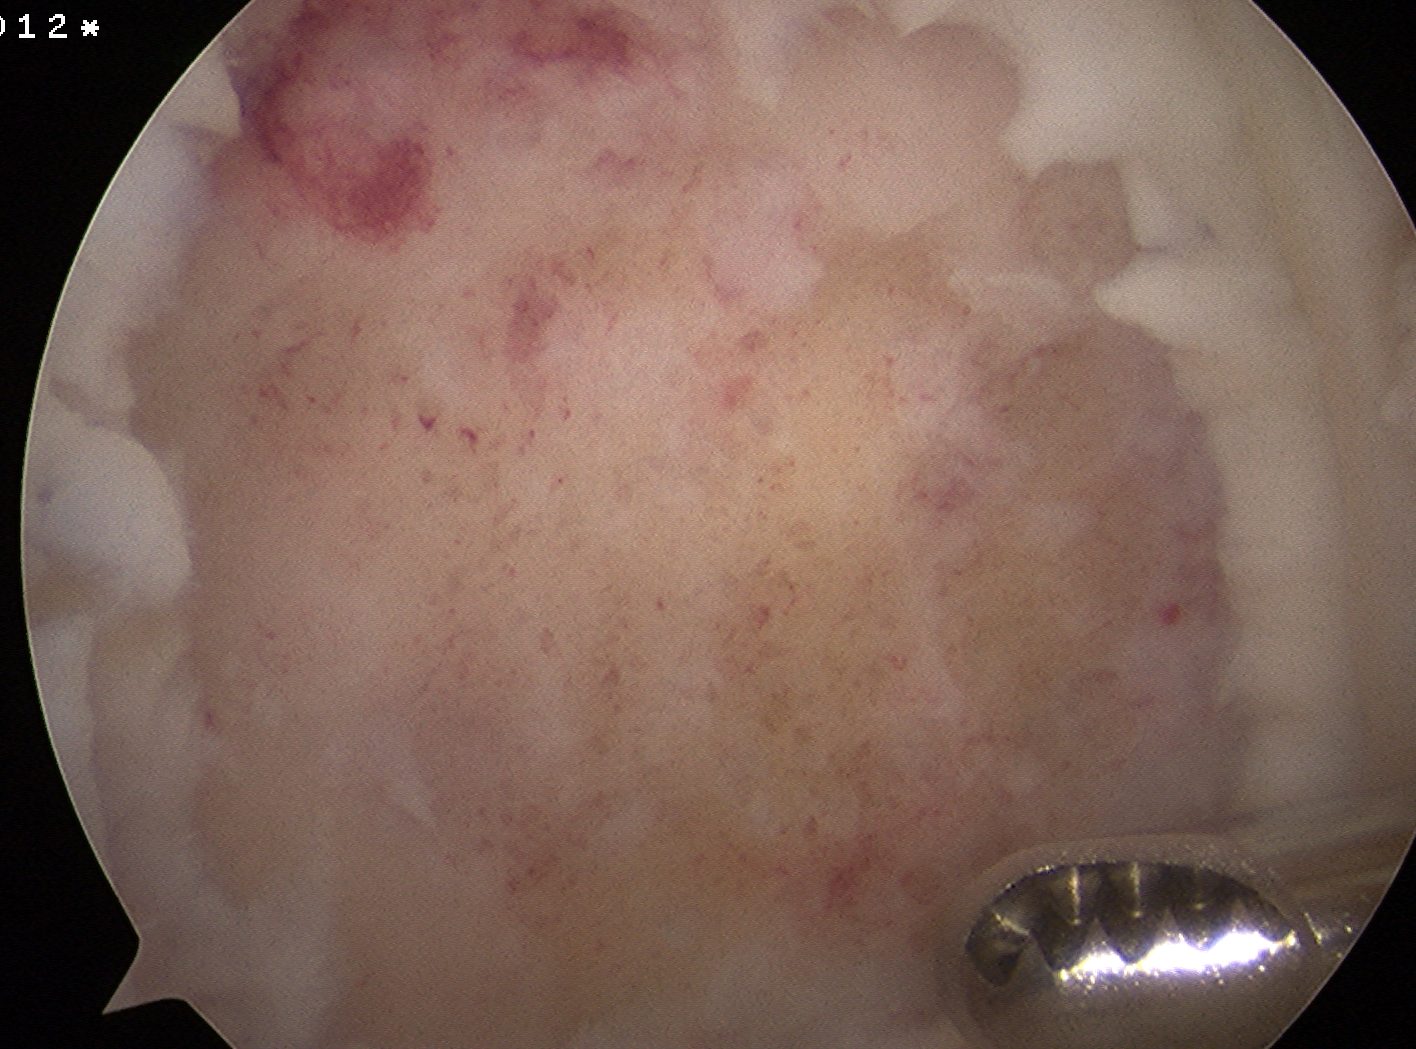

Arthroscopy

Arthroscope in lateral portal

- instrument through medial portal

- ensure can visualise entire fragment